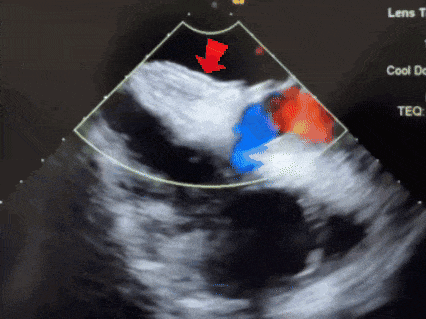

超声下,封堵器左右盘面贴合房间隔两侧

锁定后,超声下观察封堵器结构,盘面呈标准的三明治结构,成型良好

释放后超声

释放封堵器后,封堵器盘面稳固贴壁,成型良好,超声下未见分流,封堵成功。

四腔心切面下观察封堵器,左右盘面稳固贴壁,盘面平整,未影响瓣膜结构

主动脉短轴切面下观察封堵器,封堵器形态稳定,无残余分流